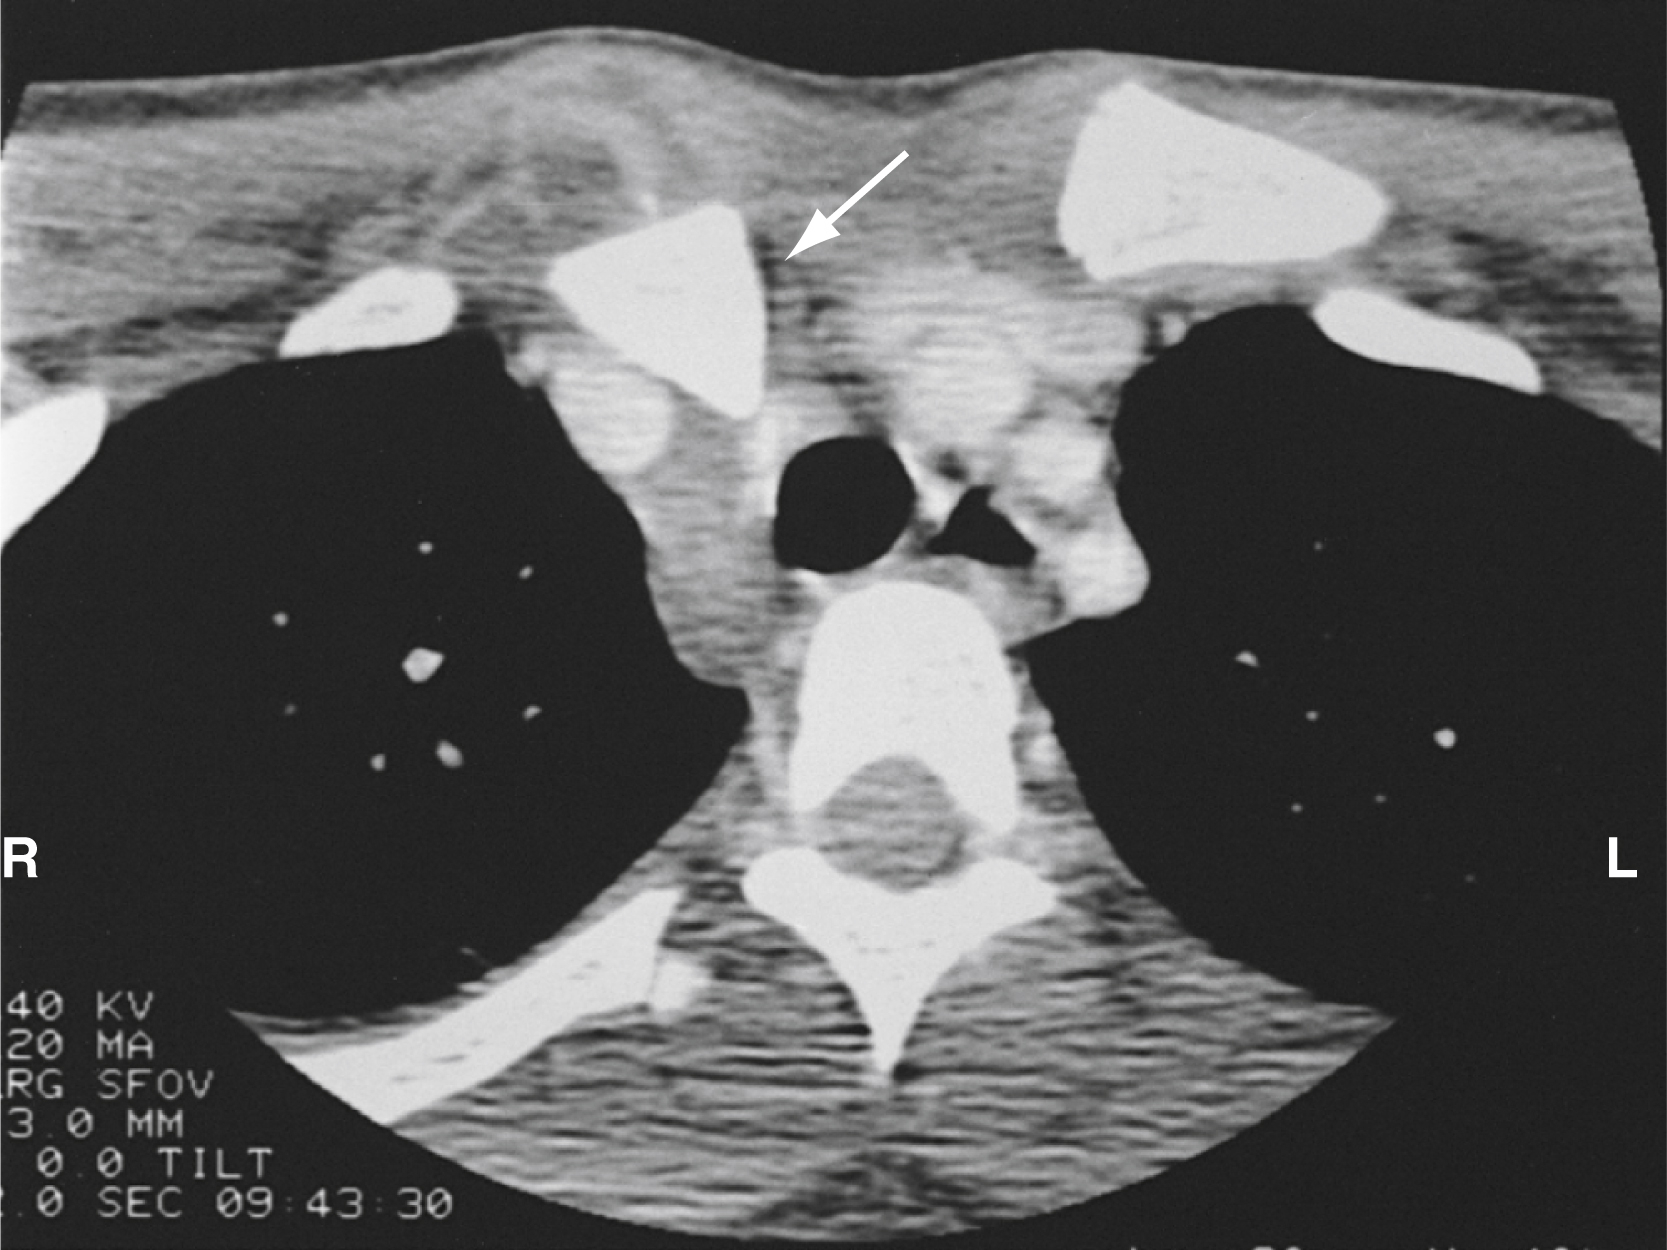

Although diagnosed clinically, sternoclavicular dislocation requires radiological confirmation. Findings on standard anteroposterior, oblique, and specialized (40-degree cephalic tilt) SCJ views are challenging to interpret. These dislocations and associated injuries are best visualized by a chest CT angiogram ( Fig. 45.16 ). POCUS can be a useful bedside adjunctive test.

This computed tomography (CT) scan shows posterior dislocation of the right sternoclavicular joint (SCJ; arrow ) with compression of the superior mediastinum.

Courtesy Donald Sauser, MD.